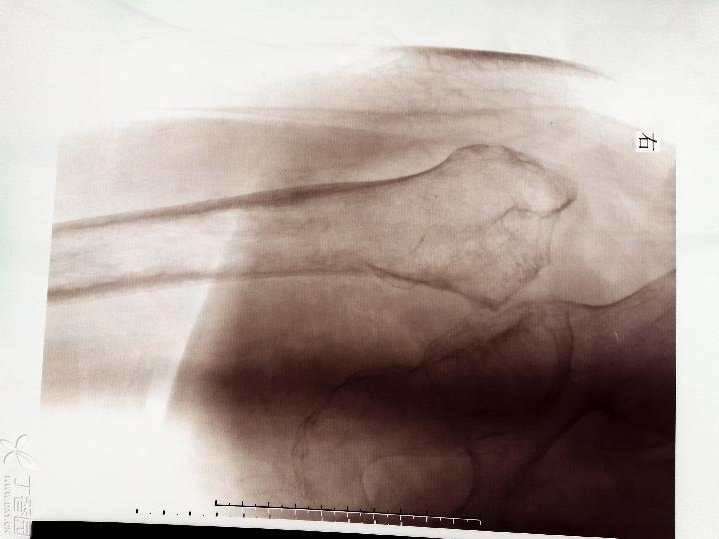

查体:心肺腹未见明显异常,右下肢短缩3厘米,右髋关节活动受限,右下肢无明显水肿,无明显感觉异常,膝上10厘米右侧大腿周径较左侧减少约2厘米,右小腿周径较左侧减少约1厘米,末梢血运好好。X片如下,右股骨颈陈旧性骨质,髋臼侧及股骨侧继发骨质疏松。CT检查显示右股骨颈骨质,股骨近端骨质未见明显破坏。

CT测得股骨头直径约46mm,股骨小转子下10厘米髓腔左右径约17-18mm,